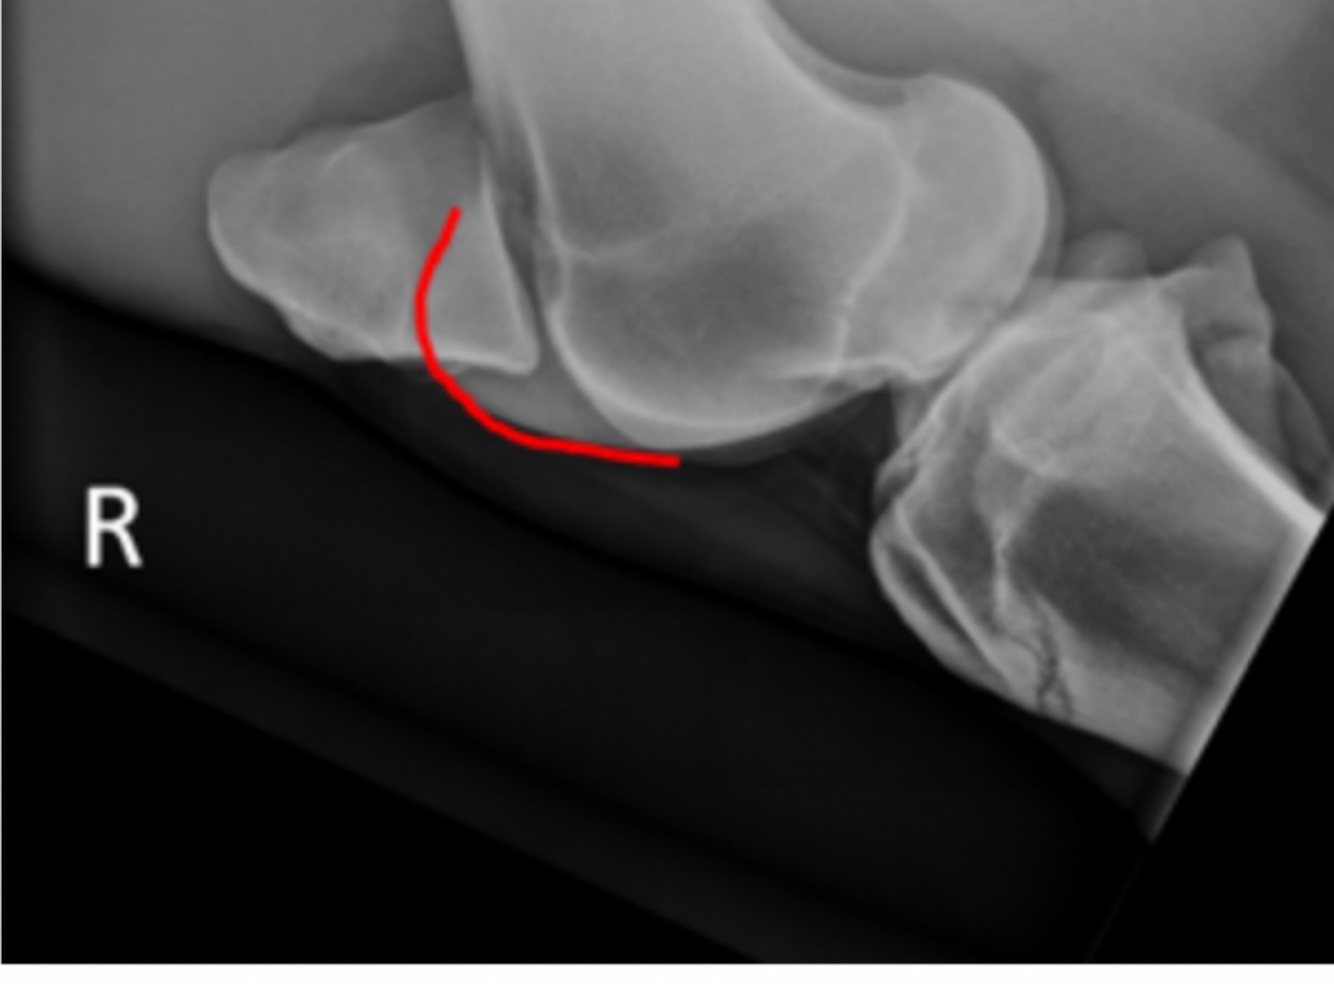

Q

What bony prominence is outlined in the image

A. Medial condyle

B. Lateral condyle

C. Medial trochlea

D.lateral Trochlea

A

C.